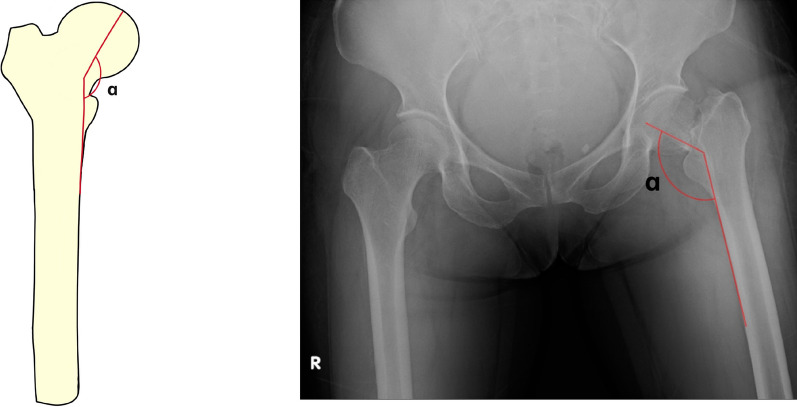

Garden Index in the anteroposterior view: the Garden Index is calculated as the angle between the central axis of the trabeculae on the medial side of the femoral neck and the cortical line on the medial side of the femoral shaft in an anteroposterior hip X-ray (Fig. 1). The Garden Index of the affected side was measured twice consecutively by three experienced orthopedic doctors (designated as A, B, and C). Three measurements for each patient were taken by each doctor, and the average of their individual measurements was determined. Subsequently, the averaged measurements of all three doctors were calculated. This procedure was then repeated for a second round of measurements.

Fig. 1.

Measurement of the Garden Index: (Left Section) Schematic Diagram: This panel illustrates the methodology employed for measuring the Garden Index. The angle under scrutiny is denoted by the Greek letter α. The angle is measured between the central axis of the trabeculae on the medial side of the femoral neck and the cortical line on the medial side of the femoral shaft. (Right Section) Preoperative Anteroposterior Radiograph: This panel shows an actual preoperative anteroposterior X-ray image of a hip with a femoral neck fracture. The angle in question is similarly labeled as α